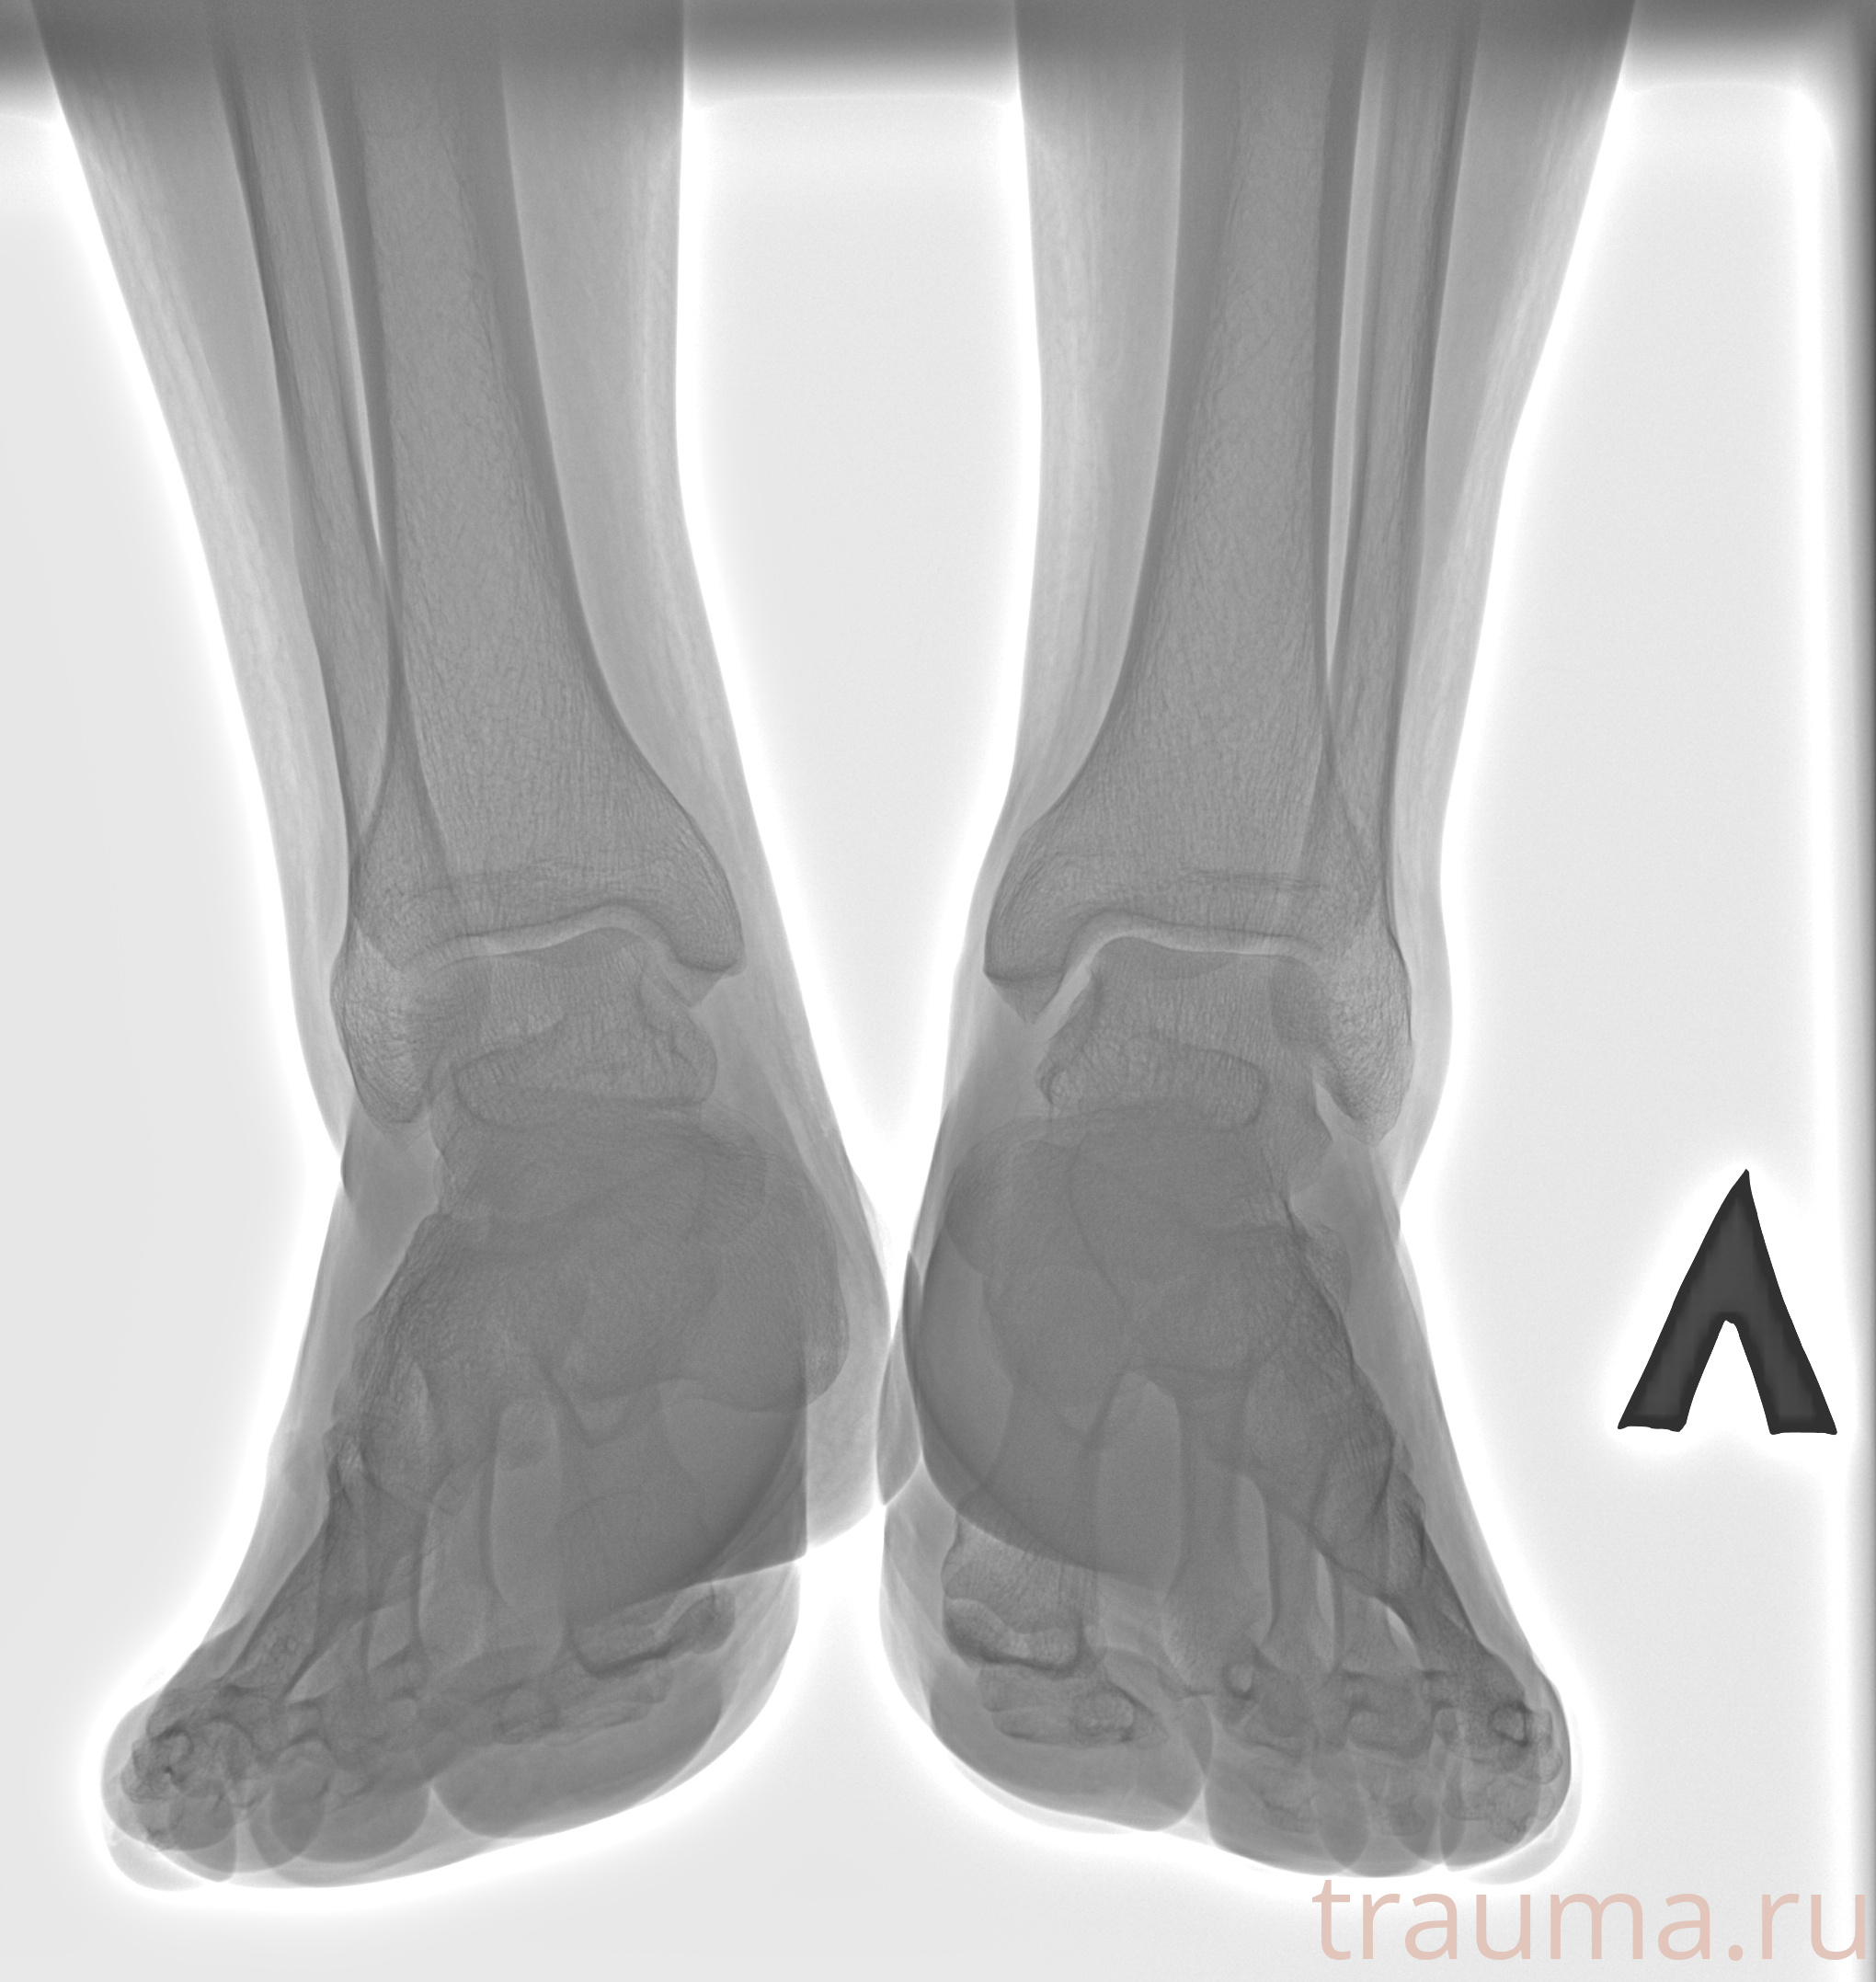

Рентгенограммы

Рентген на дому: по вашему адресу приезжает врач-рентгенолог, травматолог-ортопед с мобильным рентгеновским аппаратом, проводит диагностику травмы или заболевания, делает необходимые рентгенограммы, дает рекомендации по дальнейшему лечению. Получить качественные снимки в домашних условиях возможно благодаря уникальной методике, разработанной МосРентген Центром для института  Склифосовского